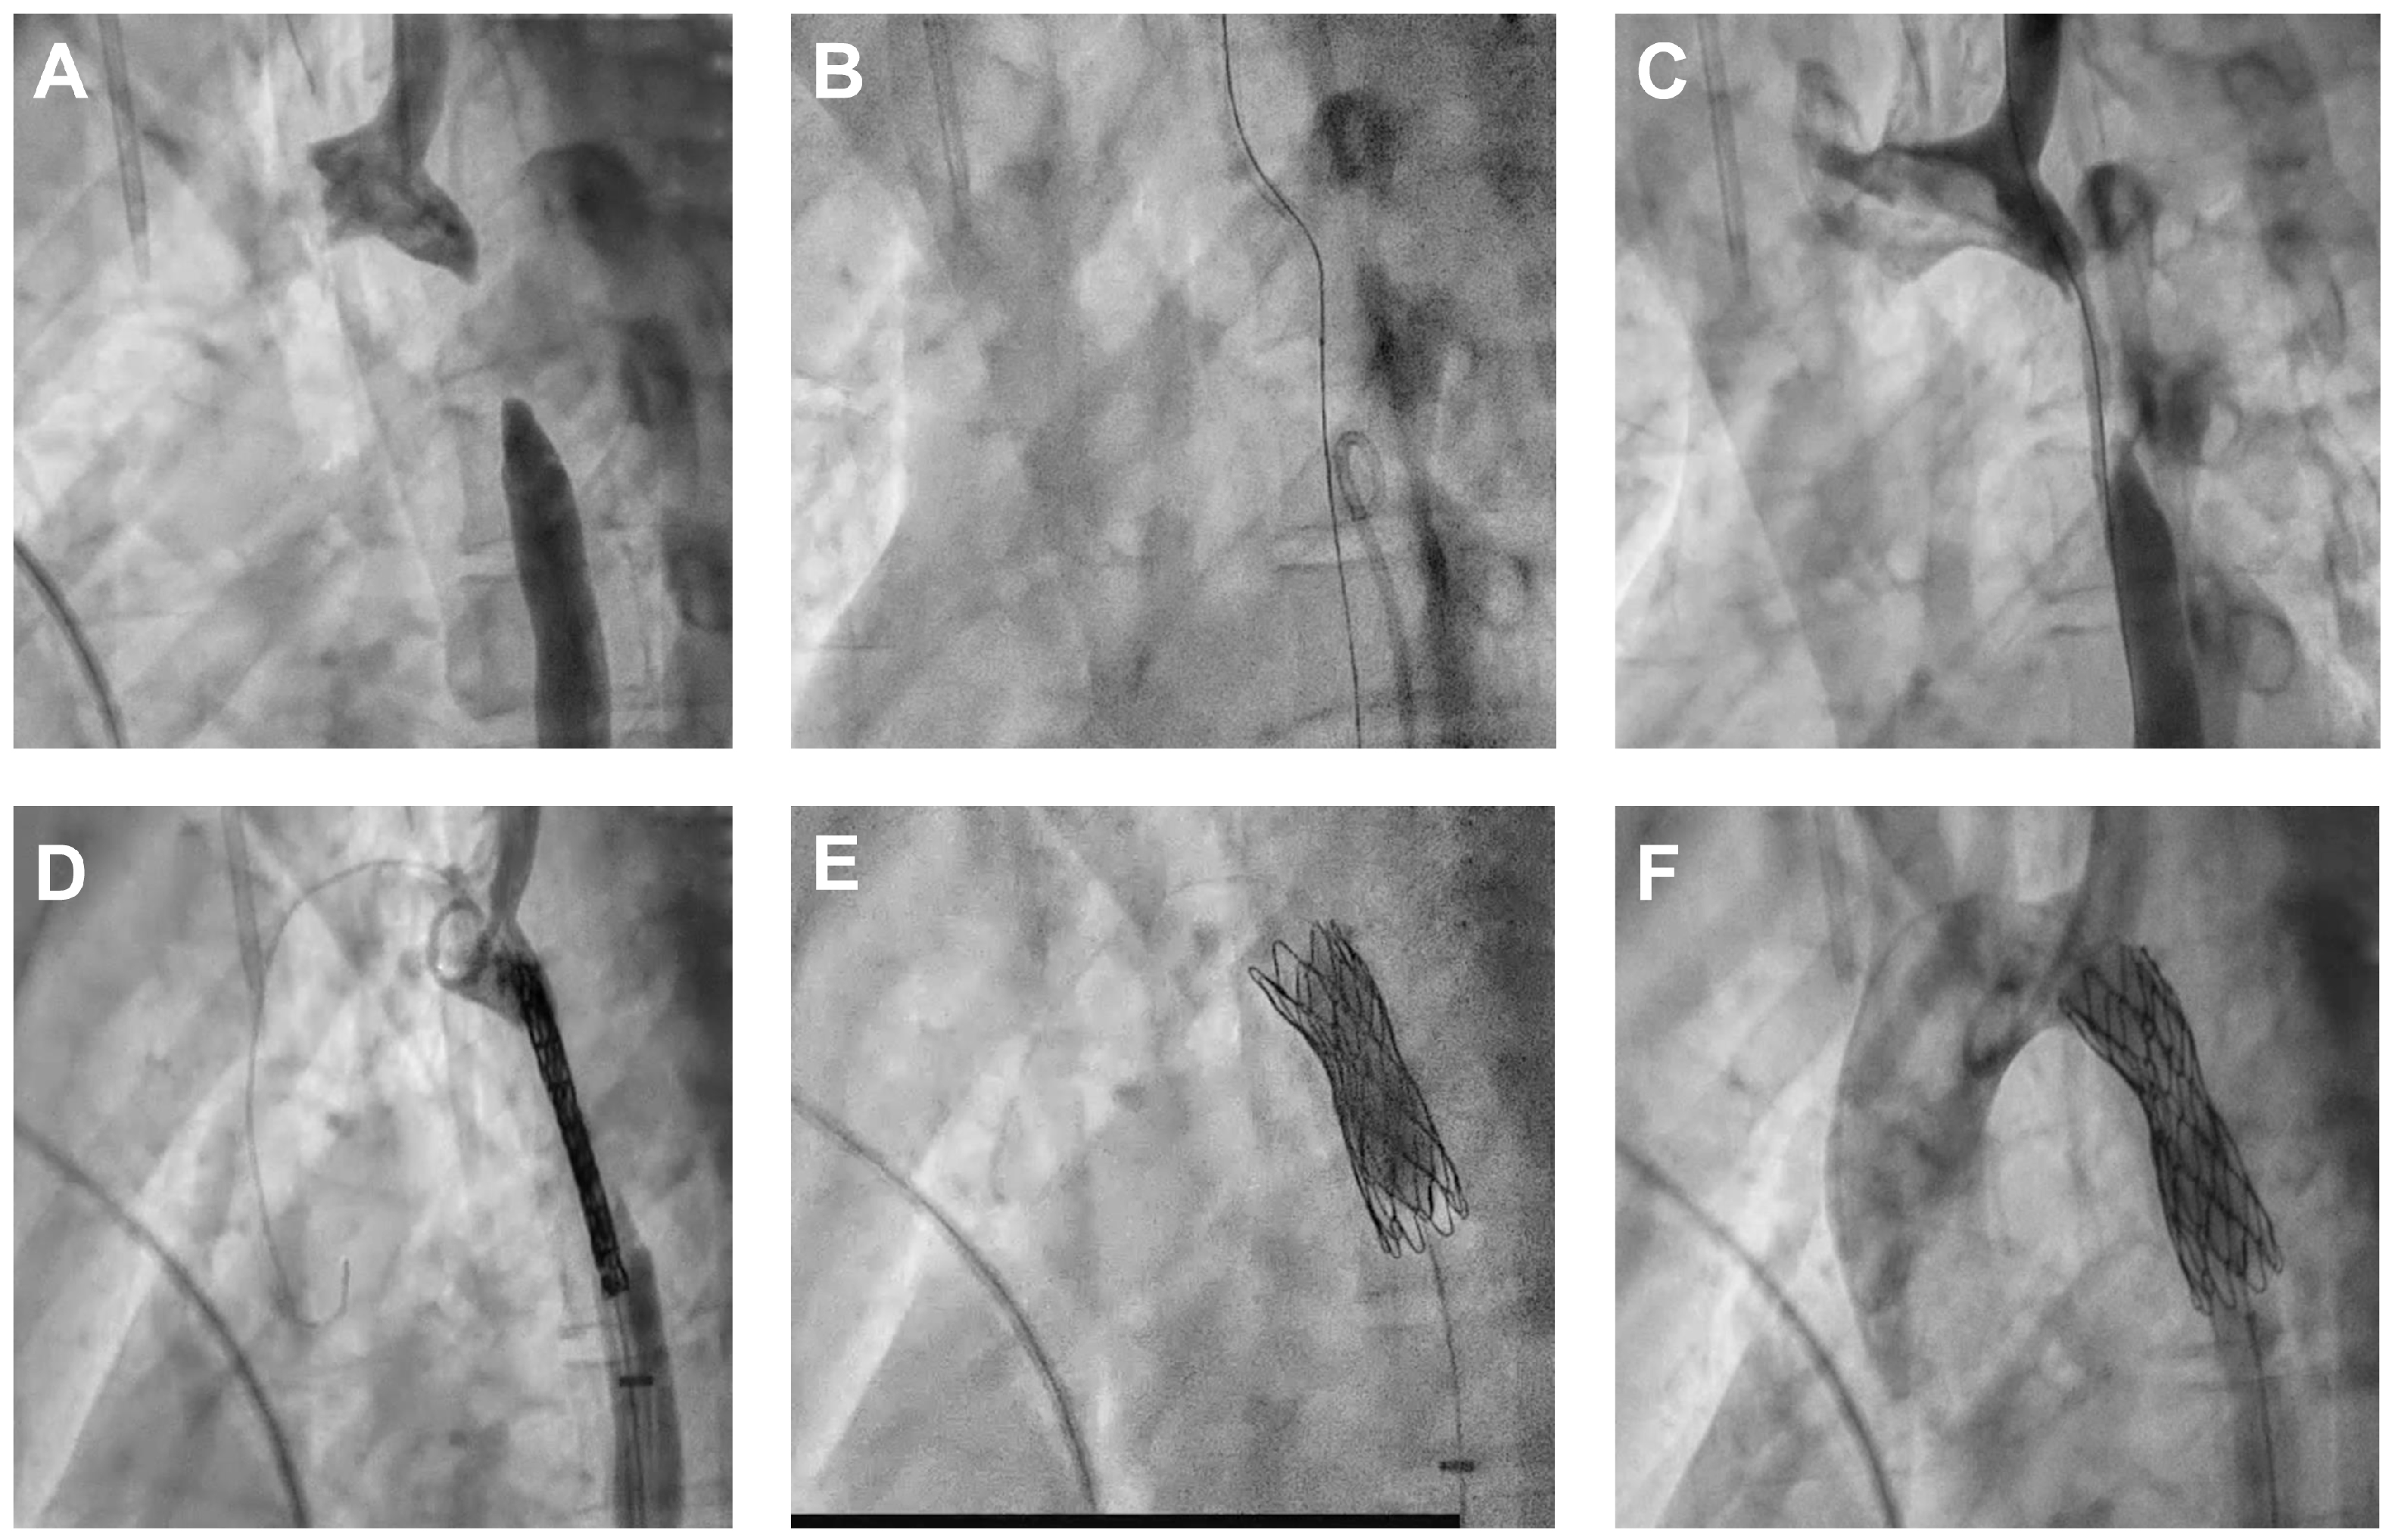

2.2.1. Core Steps of Endovascular Technique for AAA

2.2.2. Crossing the Atretic Segment

2.2.3. Balloon Angioplasty

2.2.4. Stent Placement

2.2.5. Branch Vessel Management

2.2.6. Imaging and Hemodynamic Assessment